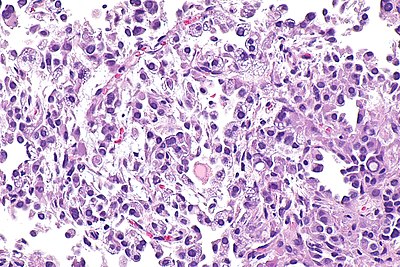

Pneumocytoma -- high mag.jpg

Pneumocytoma